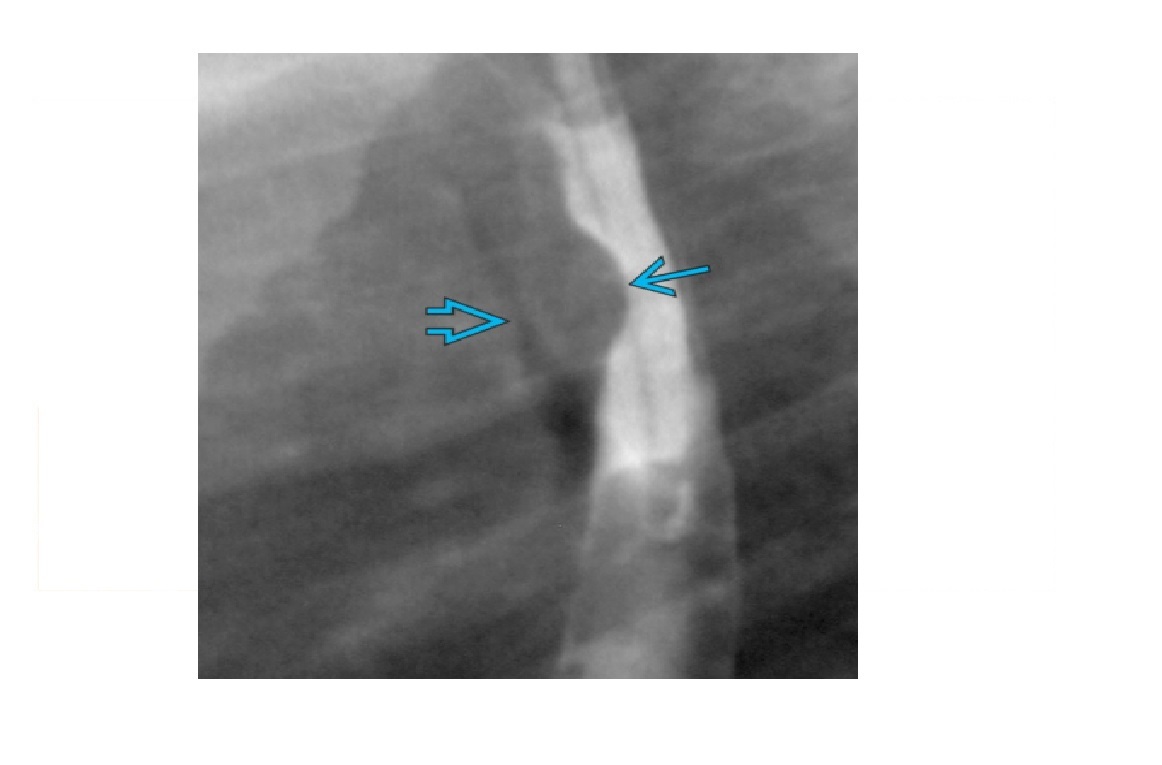

Zenker Diverticulum

Outpouching with rounded contour posteriorly in the neck is above the cricopharyngeus muscle

In hypopharynx!!!

Site of weakness is the Killian dehiscence - between the inferior pharyngeal constrictor muscle and cricopharyngeal muscle